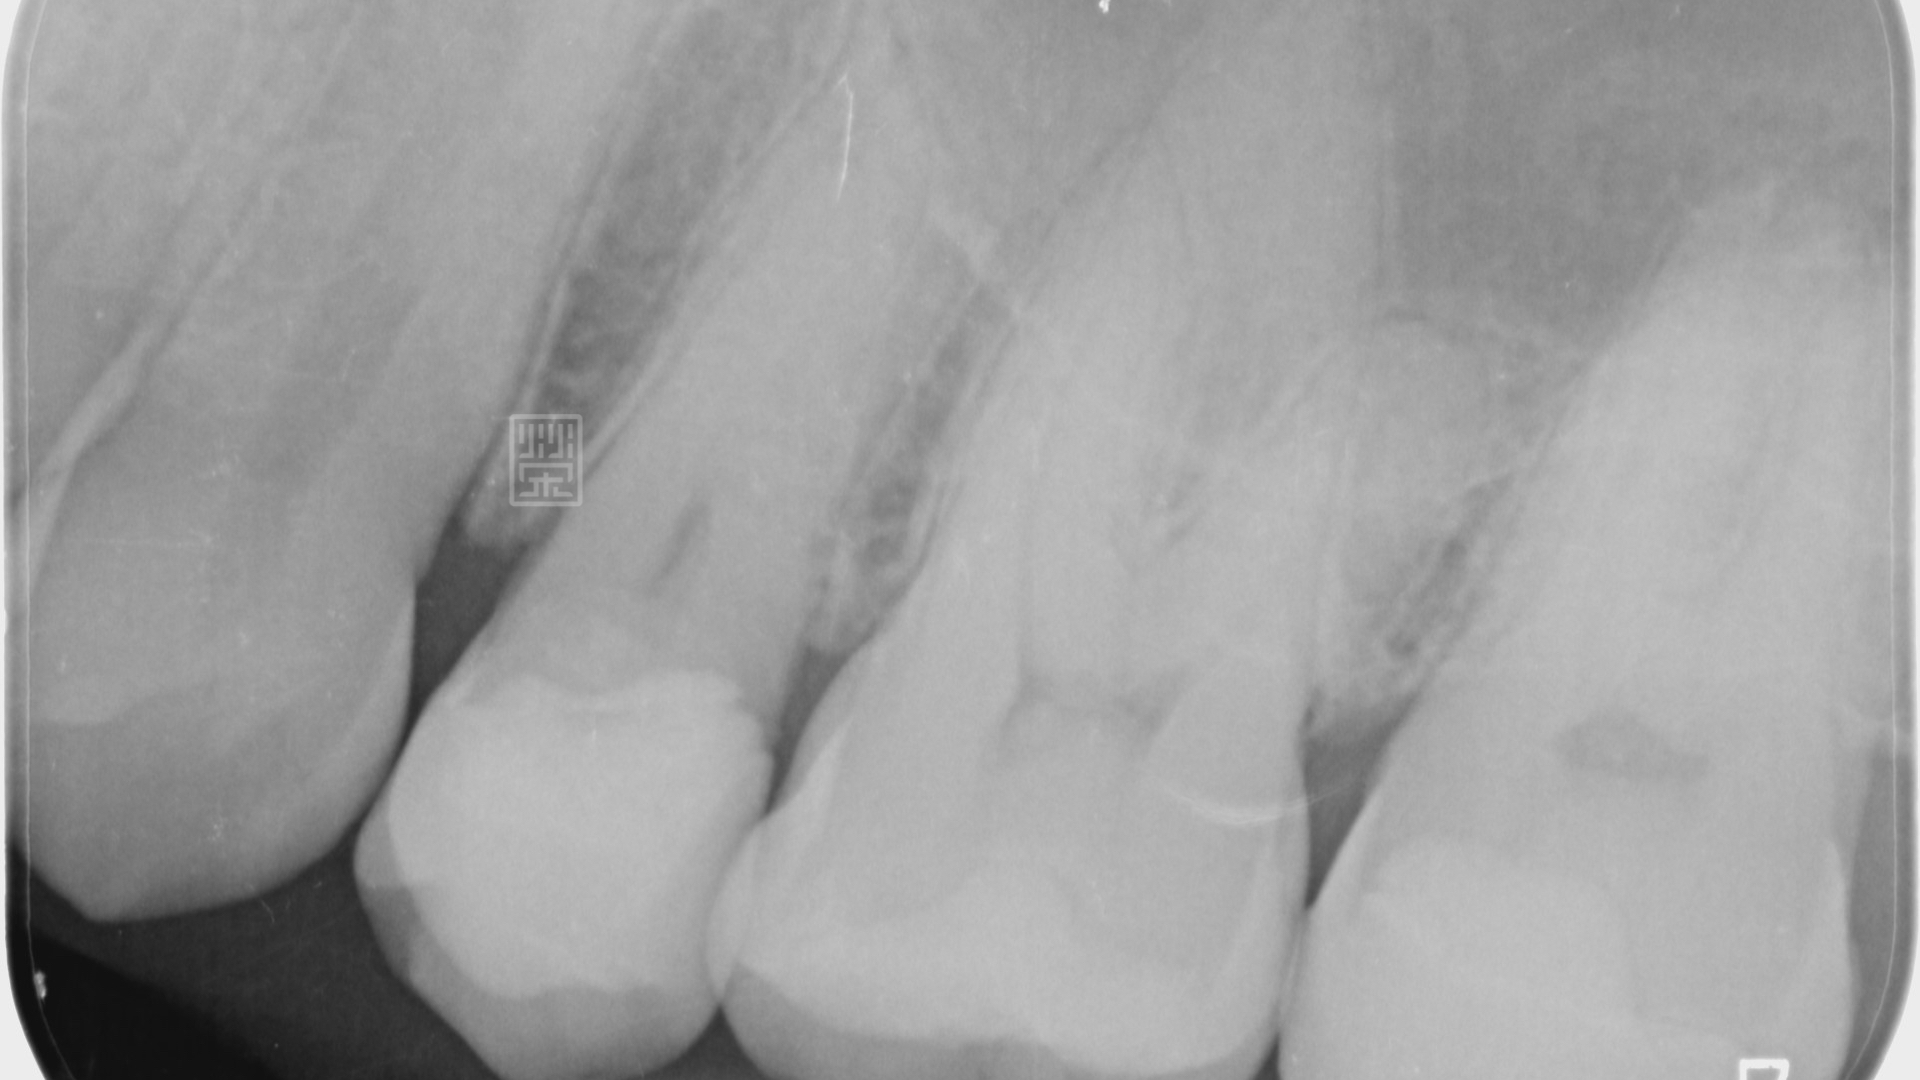

X光檢查下,雖然咬合面的蛀洞小,但是下方有很嚴重的蛀牙